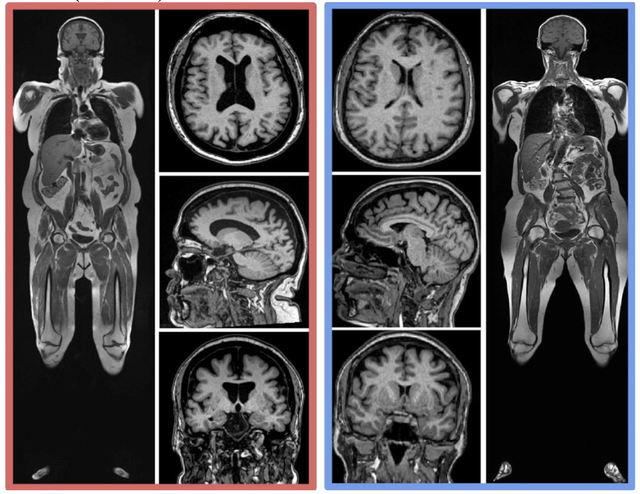

来看看两位61岁女性的核磁共振成像,左边人的内脏脂肪和皮下脂肪含量均较高,右边这位属于正常水平。可以明显看出,左边人的脑体积要比右边人的小,具体表现为脑室扩大、沟回增宽。

△高体脂脑体积缩小示例